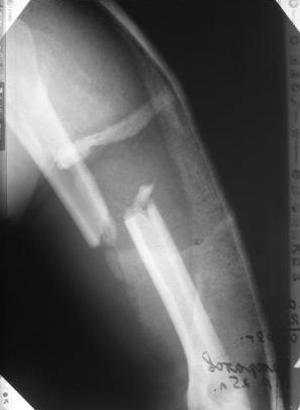

[Ortho] Перелом н\3 плечевой кости. Тактика лечения?

Да, как раз блокированная пластина и стоит, не синтезовская метадиафизарная, Рыбинская, но на порядок дешевле, а профилактика всех осложнений - в данном конкретном случае, начало ранней на вторые сутки - после удаления дренажа разработки движений в смежных суставах. Если же идти с ревизией т.е. всё равно, открыто как вариант небольших разрезов при поперечном переломе можно и комбинированный мос (см.на вкладыше), хотя думаю для такого способа перелом всётаки низковат.